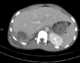

Ruptured amebic abscess